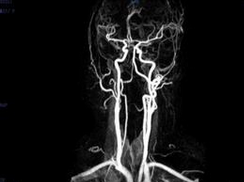

3.MRI成像

可消除颅骨底对观察肿瘤的影响,从矢、冠、轴三维方向观察肿瘤形态与相邻结构关系。肿瘤呈等T1和长T2不均信号影,轮廓不规则,注药后明显强化,边界清晰。